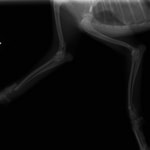

症例3:キルシュナーワイヤーのピンニングによる整復

ペルシャ猫 11ヶ月齢 雄

他院にて左大腿骨遠位の成長板骨折(salter-harrisⅠ型)が認められており、治療相談を目的として来院。当院にて、キルシュナーワイヤーを用いたピンニングにより骨折部位の整復を行いました。術後の経過は良好で、現在も経過観察中です。

術前レントゲン

術後レントゲン